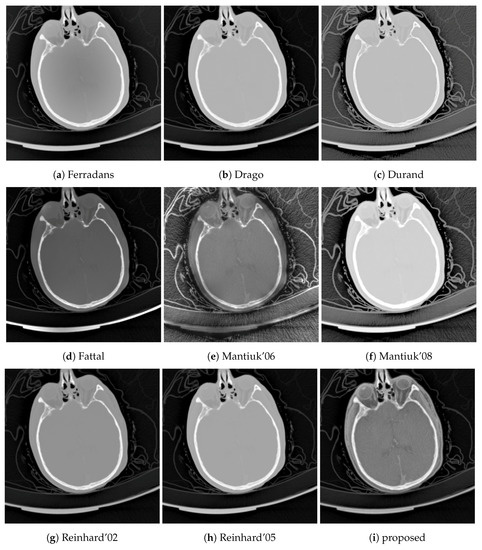

The results of our proposed algorithm are demonstrated in two ways. First, it has been compared to 8 different tone mapping operators, Ferradans [24], Drago [22], Durand [19], Fattal [21], Mantiuk ’06 [38] and ’08 [25], and Reinhard ’02 [20] and ’05 [23], using two post-mortem CT examples, a head and a chest CT. Second, the effects of changes of the algorithm parameters are depicted in two image montages, using the above-mentioned chest CT and a color photo of a ship, in Figure 4. The purpose of the ship image is to demonstrate that the algorithm is not specific to CT images. The image is an RGB image which was transformed to HSV color space [9], and the V component was processed using 256 discretization levels.

These descriptors above are used to compare the tone mapping operators to the proposed algorithm in two cases: a chest CT where the low tissue densities (lungs) are significant, and a head CT where the medium densities (white and gray matter) play an important role.

Next to the structural similarity, gradient magnitude and image entropy are also reported. These three quantitative results are presented in Table 2, while the tone mapped images are shown in Figure 5 and Figure 6.

Traditional TMOs offer dynamic range compression with low noise but good local contrast. These operators perform well for selected sub-problems, usually either for low densities (lung) or for high densities (bones). The challenge for these algorithms is to reproduce good local contrast for medium densities (soft tissues) where the contrast is already low in the source. This situation is common in head CTs where the soft tissue contrast is poor.

TMQI offers structural similarity maps at various resolution levels. Figure 9 shows the finest resolution structural similarity maps of the different tone mapping operators using the head CT example. The advantage of the proposed method is that it has better structural similarity for medium densities, e.g., white and gray matter in the brain, than the alternative methods which mostly perform well outside of the skull.